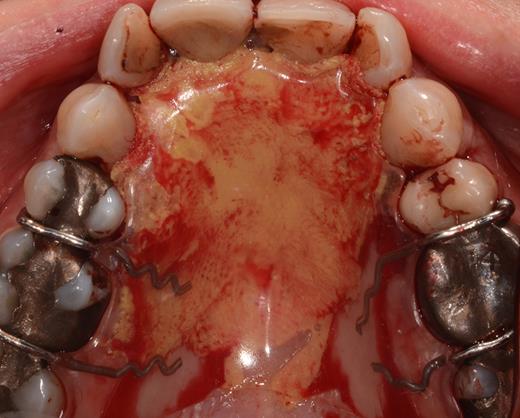

After a sulcular incision on the palatal side from teeth 15 to 25 and an incision in the midline of the palate omitting the incisive papilla and the two orifices of the NPD, two full-thickness mucoperiosteal flaps were raised. Thereafter, the incisive papilla and the whole contents of the incisive canal were enucleated (Figs 4–6). The bony incisive canal was filled with autologous bone harvested from the palatal region (bone scraper) (Fig. 7). A tension-free primary wound closure was achieved by moving the palatal flaps to the midline using single button and interdental vertical mattress sutures (Monocryl 4-0, Ethicon, Johnson & Johnson, USA) (Fig. 8). To avoid wound dehiscence and hematoma, an iodoforme gauze and a palatal plate were applied (Fig. 9). The patient was instructed to rinse three times a day with 0.1% chlorhexidine (formula hospitalis) for 2 weeks postoperatively. Sutures were removed after 14 days.

Filling of the incisive canal using autologous bone harvested from the palatal region.